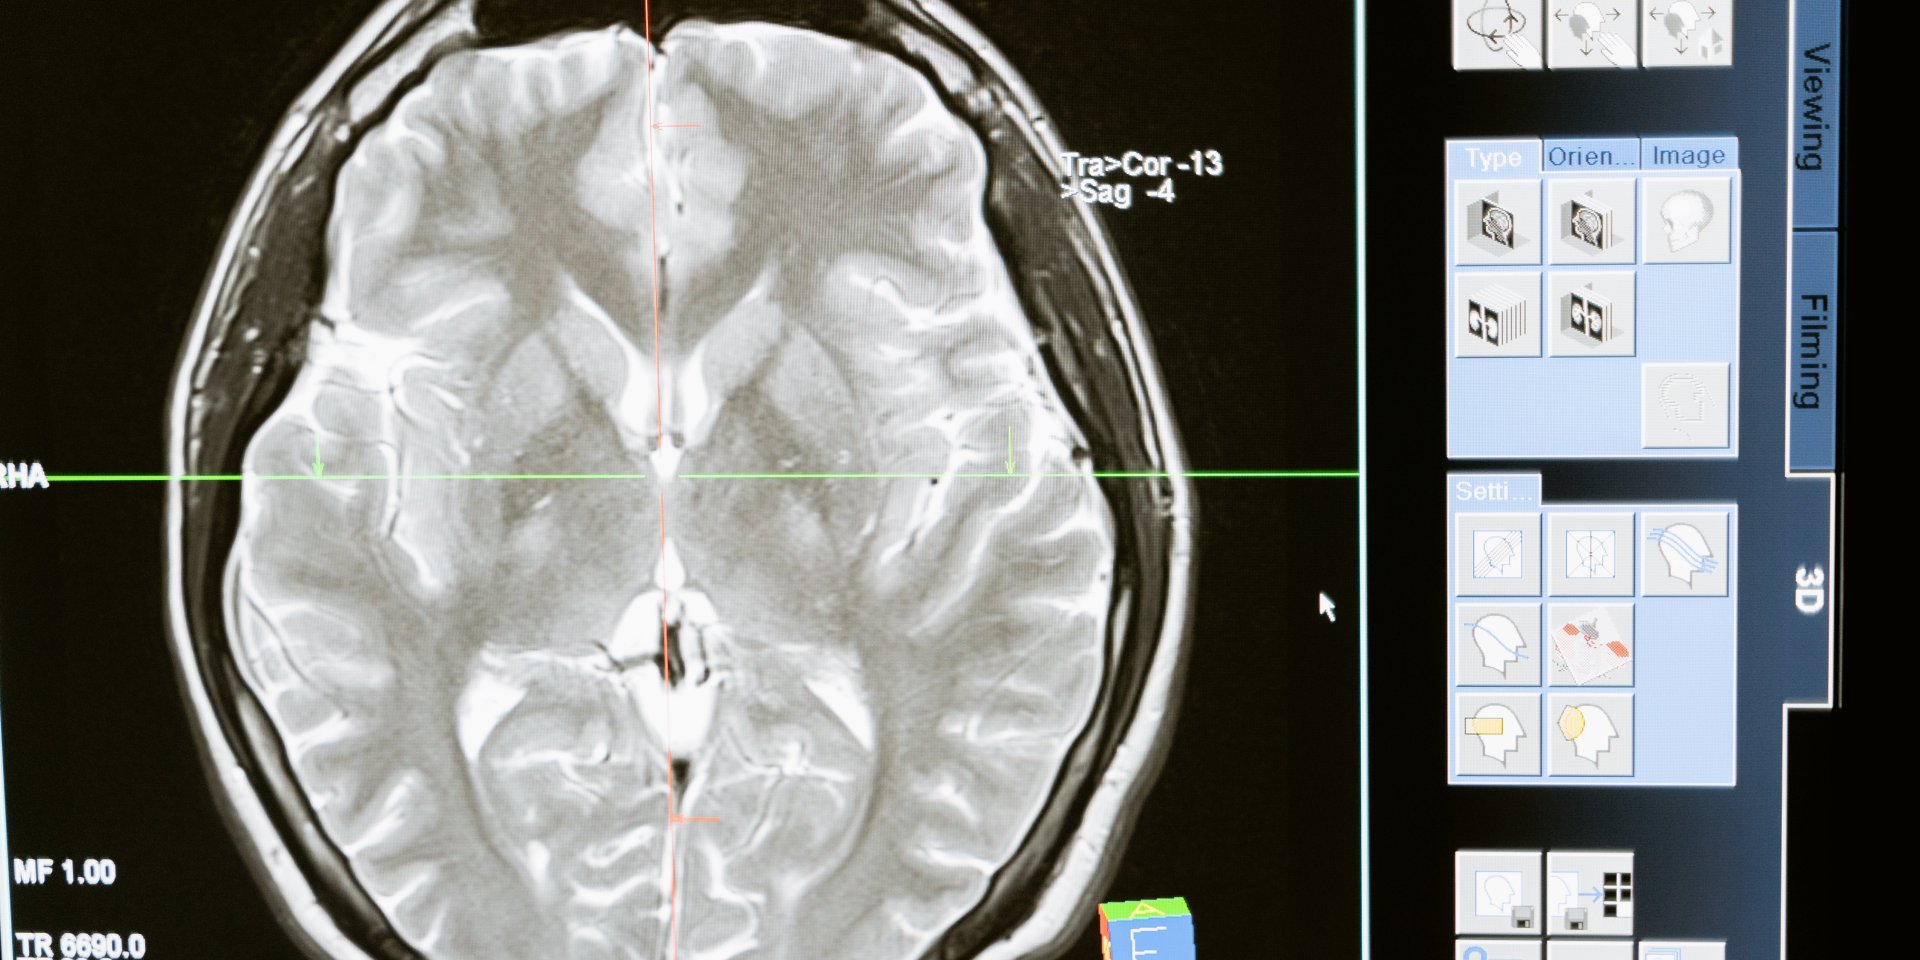

Китайская компания Neuracle Medical Technology получила первое в стране одобрение для коммерческой продажи мозгового импланта, который восстанавливает движения руки у пациентов с травмами спинного мозга.